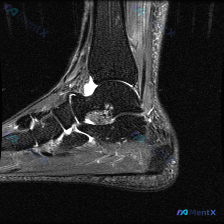

刚整理完一份踝关节MRI(矢状位T2加权序列)的读片资料,挺有启发的,分享一下完整分析思路。 病例影像核心信息 本次分析的影像为踝关节矢状位T2加权MRI,核心发现如下: 1. 骨骼结构:胫骨远端、距骨、跟骨、舟骨等轮廓清晰,未见骨皮质中断、错位,视野内无明显骨髓异常高信号,胫距关节间隙无明显异常,...

拿到这张踝关节MRI矢状位T2加权影像,问题提示是「软组织积液」,整理一下完整的读片和分析思路给大家参考。 一、先整理影像基本信息和核心发现 这是一张对比度良好的踝关节矢状位T2加权(大概率脂肪抑制)序列,能清晰看到胫骨远端、距骨、跟骨等主要解剖结构,没有明显伪影。 系统性读片下来的异常发现主要有三...

今天分享一例踝关节MRI读片,针对提问的「软组织积液」整理了完整分析思路,分享给大家。 一、病例影像基础信息 这是一份踝关节MRI的T2加权像矢状位影像,我们先整理所有客观发现: 1. 骨骼关节表现:胫距关节面轮廓基本正常,但距骨穹隆前部可见局灶性信号异常,骨软骨下方有条片状高信号影,边缘模糊;距下...

刚整理完这份踝关节MRI的读片分析,发现这个病例真的很容易踩坑,分享出来大家一起看看。 病例影像基本情况 这是一份踝关节矢状位T2加权MRI影像,先给大家梳理下所见: 1. 骨骼结构:可见胫骨远端、距骨、跟骨、足舟骨轮廓,距骨体内部可见明显异常信号影 2. 关节间隙:胫距关节间隙和软骨轮廓基本正常,...

刚整理了一份踝关节MRI读片资料,病例信息和分析思路都整理出来了,和大家分享讨论。 病例影像基础信息 本次读片基于放射影像-踝关节MRI-T2序列-矢状位,观察结果如下: 1. 骨骼结构:胫骨远端、距骨、跟骨等骨轮廓完整,无明显骨皮质中断或错位,关节间隙无明显狭窄,跟骨下缘跖腱膜附着处有局部信号异常...

刚看到一份踝关节MRI影像资料,只有一张矢状位T2加权图,整理一下我的分析思路,和大家交流一下。 先整理影像核心信息 这是踝关节MRI矢状位T2加权图像,观察各个结构的异常表现: 1. 骨与关节:距骨穹窿(距骨体前上方)可见骨软骨结构异常信号,表面不平整;胫骨远端、跟骨、舟骨轮廓完整;踝关节前间隙可...

看到这个踝关节MRI的读片请求,整理了一下资料和分析思路分享给大家: 病例影像基本信息 这是一张踝关节矢状位T2加权磁共振图像,先给大家整理一下读片结果: 1. 骨性结构:胫骨远端、距骨、跟骨等骨质信号正常,没有发现弥漫性异常高信号,也没有明确骨折线或骨质破坏 2. 关节软骨:距骨滑车关节软骨轮廓连...

看到这个踝关节MRI的读片需求,整理一下病例资料和完整分析思路,和大家一起讨论。 病例影像基本信息 这是一张踝关节矢状位T2加权MRI影像,核心发现是存在软组织积液,具体观察结果如下: 1. 骨骼情况:胫骨远端、距骨、跟骨、足舟骨骨皮质完整,没有明显骨折线,也没有广泛骨髓水肿信号 2. 关节情况:胫...

刚看到这份踝关节MRI矢状位T2加权图像,整理一下读片思路和分析,和大家一起讨论。 病例核心影像信息 这是单张踝关节矢状位T2加权图像,主要发现如下: 1. 骨骼与骨髓信号:距骨体部可见边界尚清的团片状高信号,提示骨髓水肿/骨小梁损伤;跟骨距下关节下方可见小片状高信号灶;胫距关节间隙无明显狭窄,踝关...